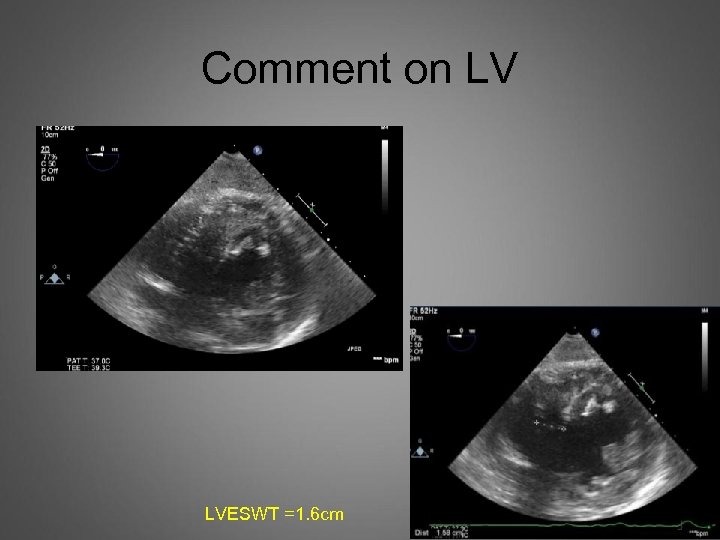

Comment on LV LVESWT =1. 6 cm

Next case LV SAX view